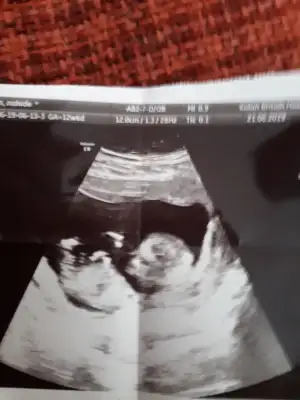

Kesin kız canım o bebiş, doktorda söylerken emin bi şekilde söylemiş.anneolmakmucızenin en son ki mesajında öyle yazıyor. Nub bariz paralel. 😁😁 olabilir arada yanılabiliriz sıkıntı yok🤗